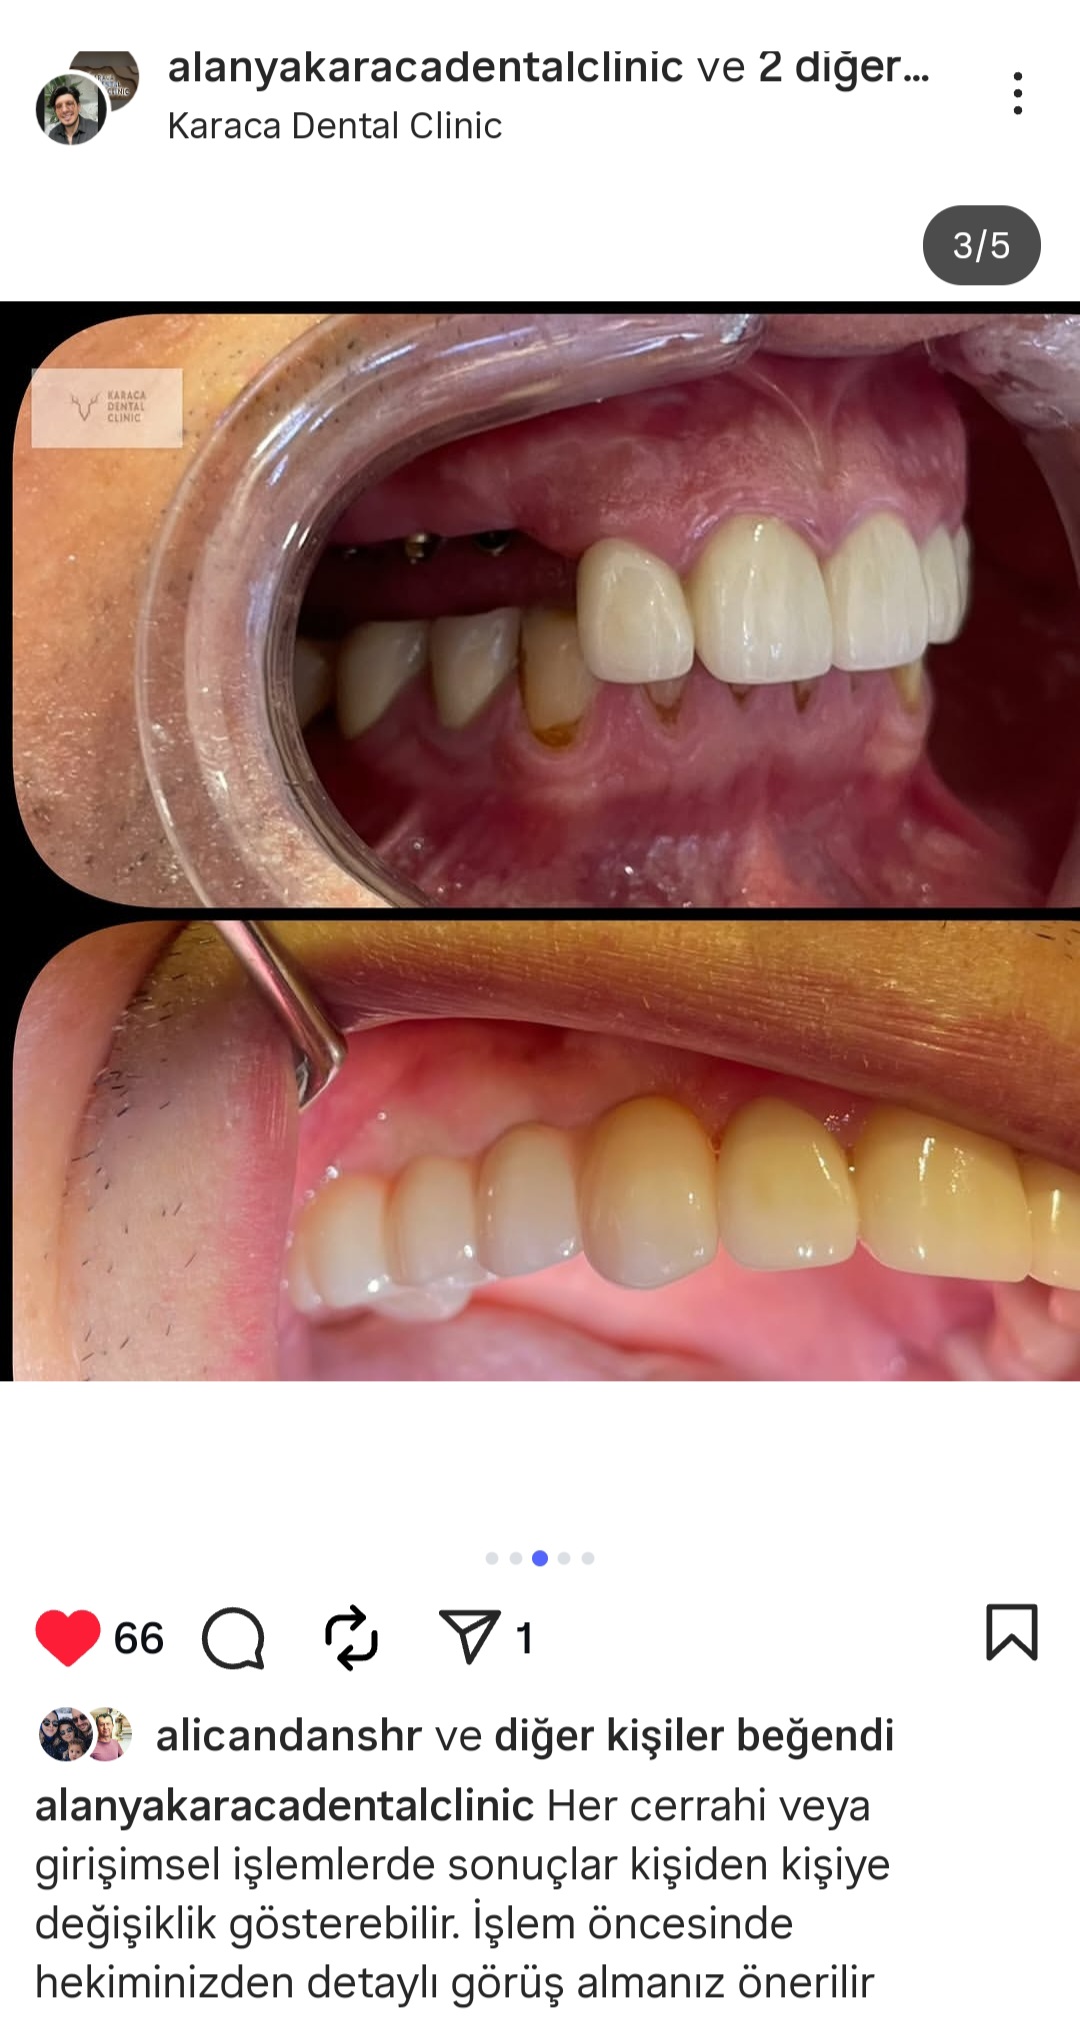

- Diş Dolgusu Kanal Tedavisi İmplant Tedavisi Çocuk Diş Hekimliği (Pedodonti) Lamina Kron Kaplama Zirkonyum Kron Kaplama Estetik Dolgu Estetik Gülüş Tasarımı Hollywood Gülüşü Diş Taşı Temizliği Air Flow Diş Temizleme Diş Beyazlatma Diş Çekimi Gece Plağı Dijital Diş Hekimliği 7/24 Diş Kliniği Hizmeti Acil Diş Kliniği Hizmeti Nöbetçi Diş Kliniği Hizmeti # HİZMETLERİMİZ #